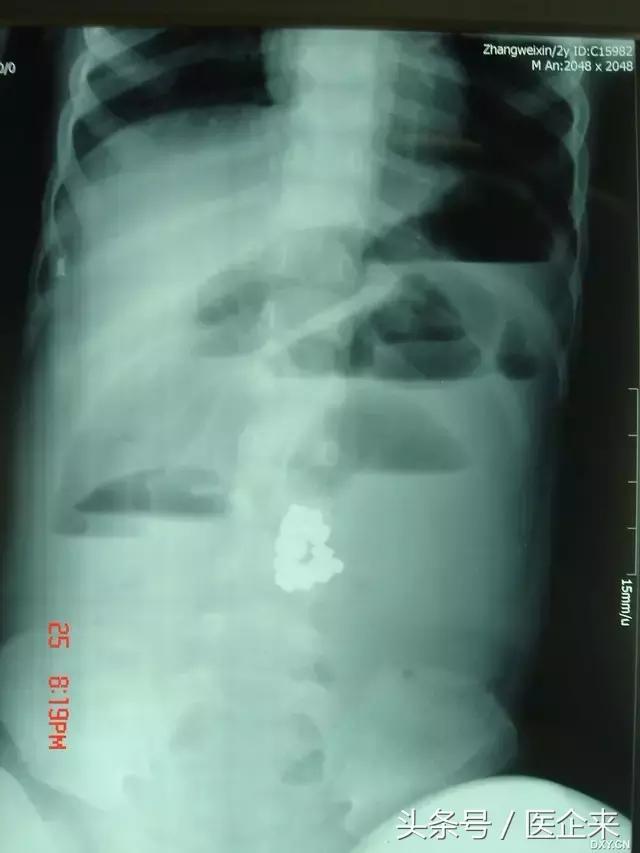

3.磁性手镯经口进入(心疼这个2岁的小宝宝,做手术要遭多大罪啊!)

取出的磁性手镯